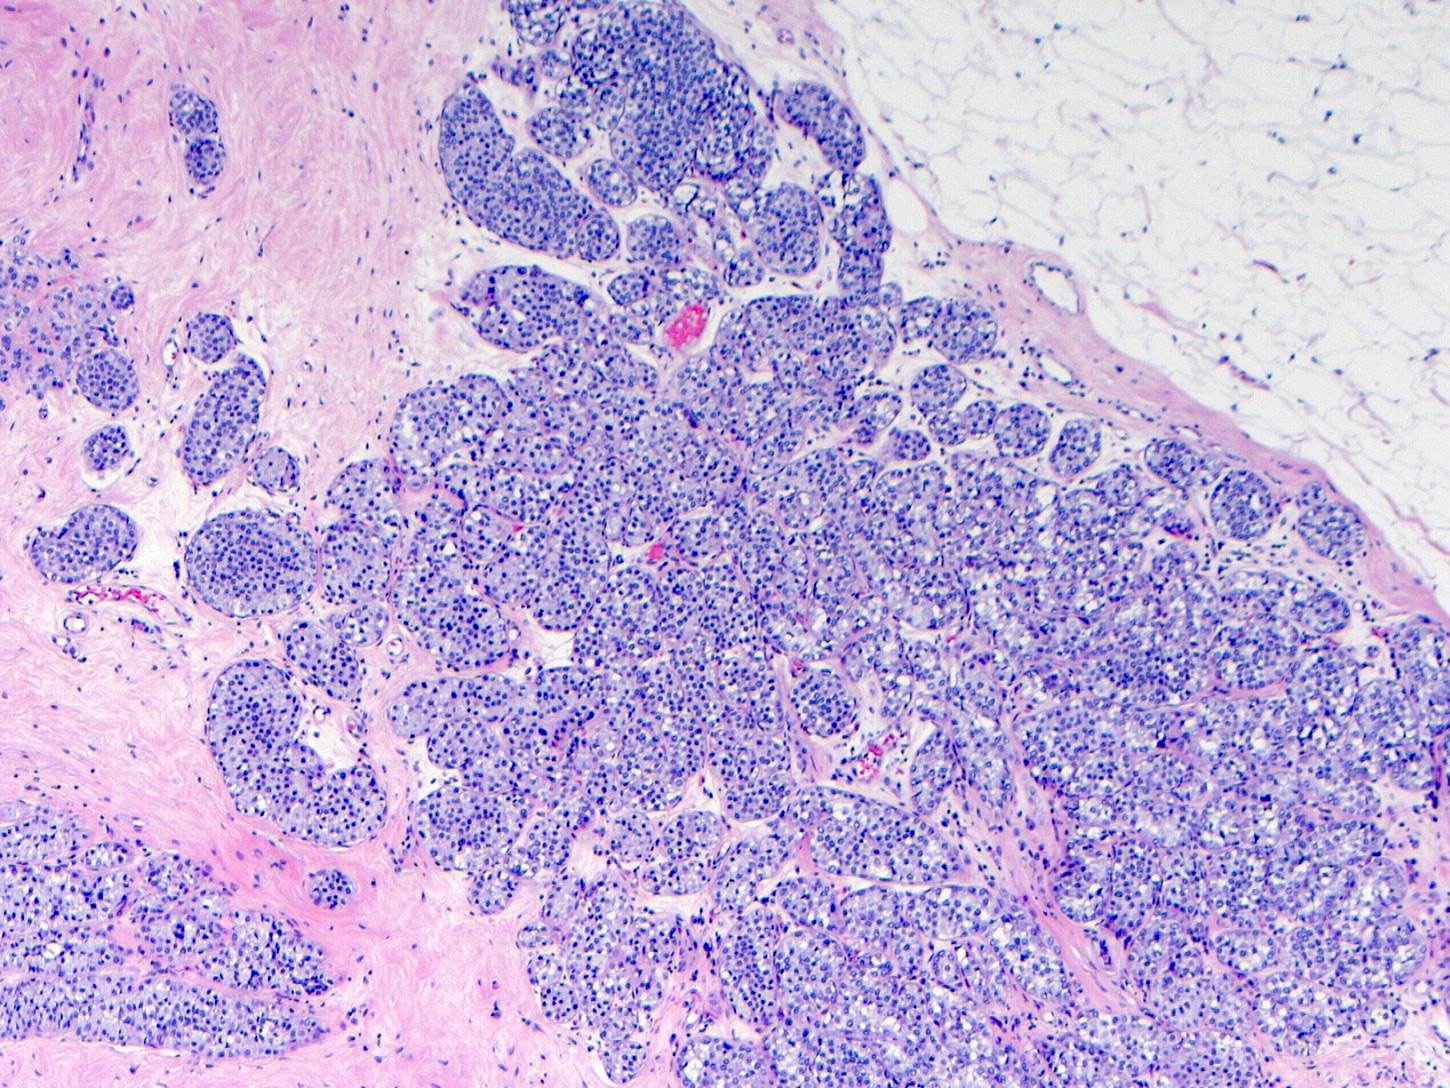

Microscopic (histologic) images

Contributed by Anna Biernacka, M.D., Ph.D.

- LCIS involves the terminal duct lobular unit (TDLU), filling and distending acini

- > 50% of the acini in a TDLU must be filled and expanded to qualify as LCIS; otherwise, called atypical lobular neoplasia

- Lobular distention is defined as the presence of ≥ 8 cells in the cross sectional diameter of an acinus

- Involved lobules may be compared with uninvolved lobules to estimate the degree of distension

- Classic LCIS cells are monomorphic, evenly spaced, loosely cohesive and do not show polarization or gland formation

- 2 types of cells are described:

- Type A: nuclei are small to slightly enlarged (1 - 1.5x size of lymphocyte) with uniform round nuclei and inconspicuous nucleoli

- Type B: nuclei larger (2x size of lymphocyte), more abundant cytoplasm and more prominent nucleoli

- Type A and B cells can coexist in the same lesion